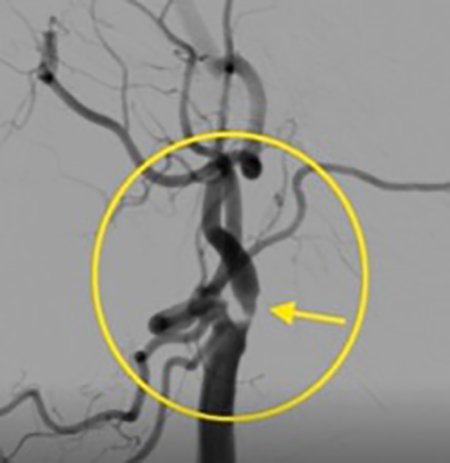

MRI/CT interpretation and Thrombectomy and stenting/ plasty for acute and recurrent stroke. Cerebral DSA

Visceral , peripheral and central arterial aneurysm embolization

Thrombectomy – mechanical , pharmacological and combined therapy for acute stroke.

Outcomes observed in patients treated with image-guided, minimally invasive vascular procedures.

Results vary by patient and condition. Images are for educational purposes only.